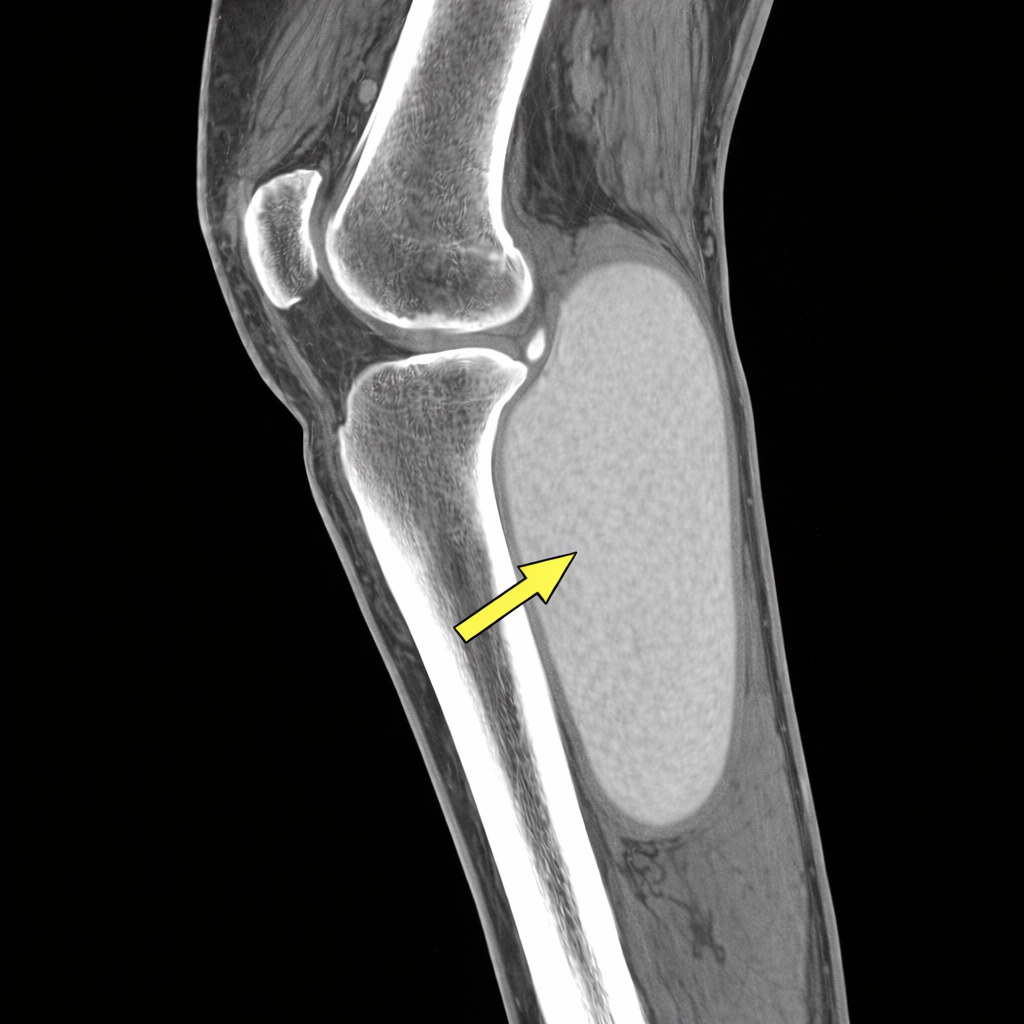

※AI生成の参考画像です

CTでは下腿後面筋間に嚢胞性病変を認め、

そこで改めて画像を精査すると、

- 膝関節包の肥厚と造影効果

- 膝関節水腫と嚢胞性病変の連続性

を認め、

下腿局所病変というより、膝関節由来の病態が示唆されました。

一方で、画像所見は前回とは明らかに異なっていました。

- 嚢胞の位置が前回とは異なり、さらに増大している

- 初診時には均一であった嚢胞内容が不均一に変化している

- 皮下浮腫は前回より明らかに増悪している

さらに造影CTでは、

膝窩よりやや遠位に、静脈の圧排あるいは血栓を疑う所見を、

明瞭とは言えないまでも認めていました。